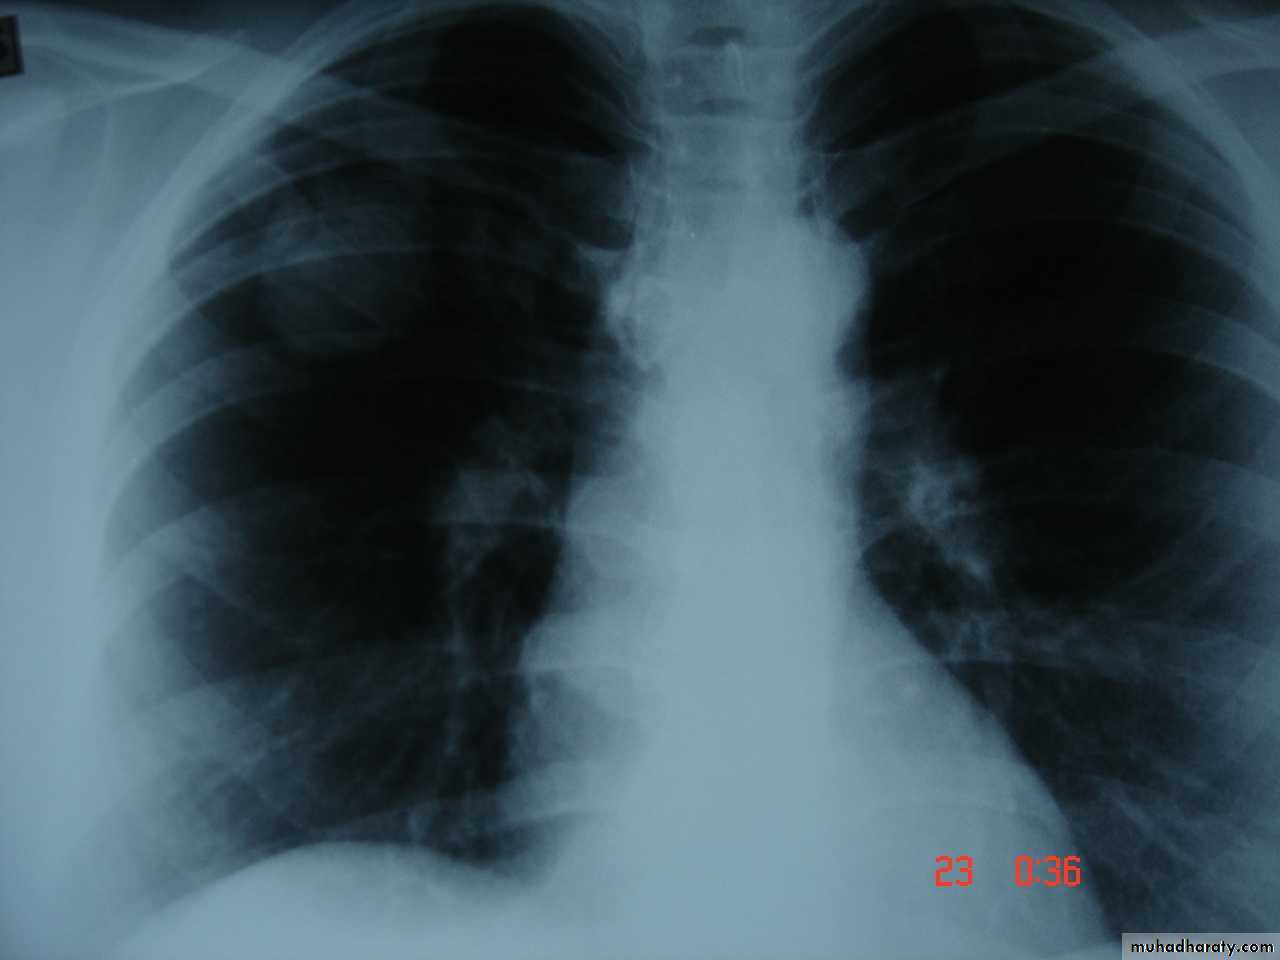

Bronchogenic Ca. cavitory lesion

• Pathology :-A-Central type is the commonest (75%).It arises in one of the main bronchi or their primary division leading to bronchial obstruction with secondary changes in the lung such as atelectasis .B-Peripheral type (25%) arises from the smaller bronchi and remains symptom less for long time .

Histologically Squamous cell Ca (SCC) 60% , smoker , centrally located ,metastasizes to mediastinal & supraclavicular LN . Adenocarcinoma (15% ) , located peripherally , more in women .Tends to metastasizes to the liver , brain ,bone & adrenals in addition to the LN Undifferentiated carcinoma (oat) cell carcinoma and large cell carcino(20-30%) which includes small cell Ca Alveolar cell carcinoma , located peripherally ,metastasizes to the liver and adrenalsRecent classification..Non small & small cell carcinoma

• Chest X-ray ,CT chest ..